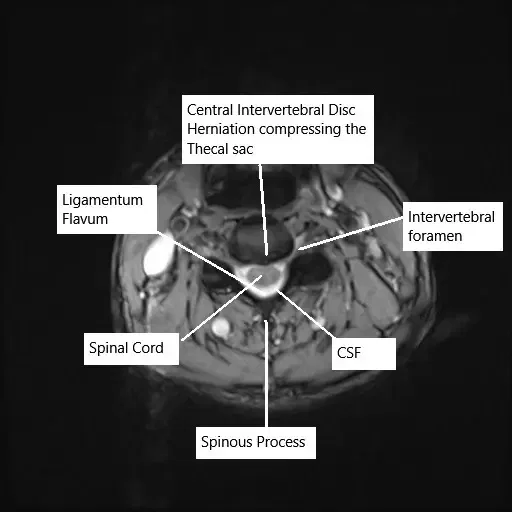

Sección axial de la columna cervical que muestra hernia discal en la resonancia magnética.

El disco intervertebral es una estructura similar a un gel que amortigua las vértebras y permite la movilidad de la columna. Con el tiempo, el desgaste, el traumatismo o cambios degenerativos, como una disminución de la hidratación en el núcleo pulposo del disco, pueden provocar hernia discal o abultamiento. Estas condiciones comprimen las raíces nerviosas cercanas o la médula espinal, causando dolor, debilidad, entumecimiento y, en casos graves, pérdida de movilidad. La obesidad, el tabaquismo, la mala postura y la tensión repetitiva son factores que contribuyen a la degeneración y hernia discal.

El diagnóstico se confirma mediante examen clínico y estudios de imagen. La resonancia magnética es el estándar de oro para identificar hernias discales, degeneración discal y compresión de la raíz nerviosa. En casos de dolor cervical o lumbar, las resonancias magnéticas revelarán la localización y extensión de la hernia, el estado de los discos y cualquier pinzamiento en los nervios o la médula espinal.